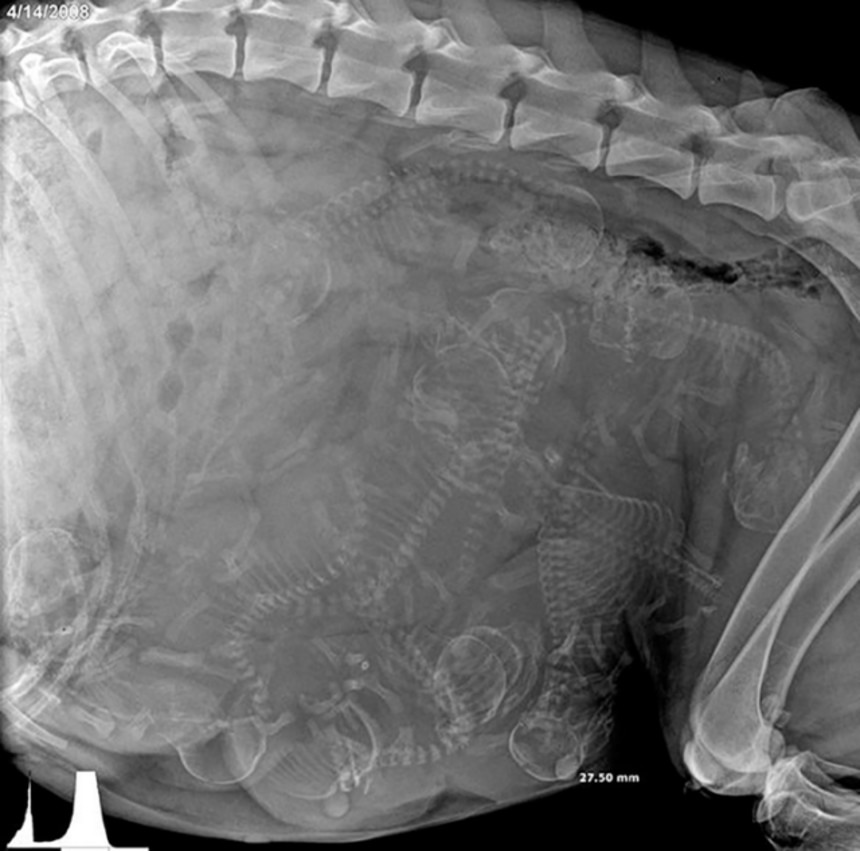

7. 妊娠したアラスカンマラミュートのお腹のレントゲン写真

image by: GoodGriefWhatsNext / reddit